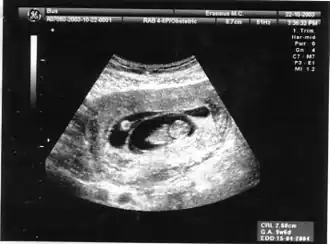

Het is van groot belang om een meerlingzwangerschap vroeg in de zwangerschap te onderkennen door een echo en na te gaan of ze monochoriaal of dichoriaal is. Vroeg in de zwangerschap is op een echo heel goed te zien welke de chorioniciteit van de tweeling is (zie foto een voorbeeld van een dichoriale tweeling, echografisch te zien door het dikke begin (delta sign) van het tussenschot tussen de beide vruchtzakken bij de baarmoederwand). Deze tweeling kan zowel monozygoot als dizygoot zijn.